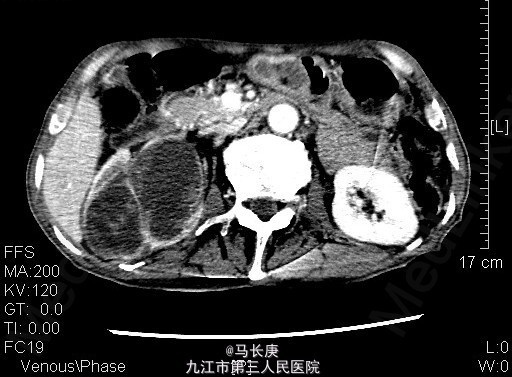

1、右上腹痛伴全程肉眼淡红血尿2月 2、患者于2月前无诱因出现右上腹痛伴全程肉眼淡红血尿,可以自行缓解,无血块、血条,无尿频、尿急、尿痛,无排尿困难,当时未引起重视,未去就医,7天前右上腹痛及血尿加重,于当地人民医院就诊,诊断为:右肾占位,现为进一步诊治于来我科进一步治疗。起病以来,一般情况尚可,近期体重明显下降。

3、查体:无明显异常 4、辅助检查:当地人民医院泌尿系CT平扫+增强:1.右侧输尿管结石2.右肾占位?(未见报告),我科fish(+)CTU:肾盂癌,侵蚀右肾包膜,左肾囊肿,慢性胆囊炎。双肾核素扫描:右肾GFR:9.5,左肾48.5

5、考虑右肾盂癌 6、入院后给予双肾核素扫描、CTU检查,考虑右肾盂癌,给予抗炎、补液、治疗。现病情平稳。 术前诊断:右肾盂癌、胆囊炎、左肾囊肿、右侧输尿管结石、贫血、低蛋白血症、胆囊炎,后行右肾癌根治术,手术顺利,术后恢复较好,术后病理示:肾恶性肿瘤(高分化肉瘤)。